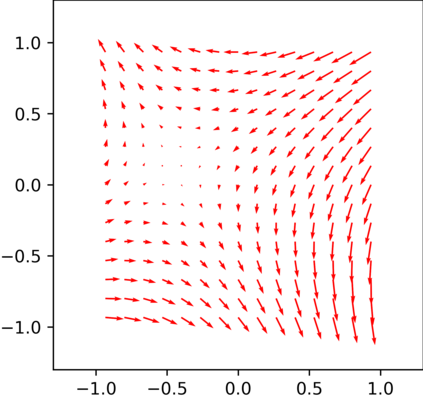

Multi-modality (or multi-channel) imaging is becoming increasingly important and more widely available, e.g. hyperspectral imaging in remote sensing, spectral CT in material sciences as well as multi-contrast MRI and PET-MR in medicine. Research in the last decades resulted in a plethora of mathematical methods to combine data from several modalities. State-of-the-art methods, often formulated as variational regularization, have shown to significantly improve image reconstruction both quantitatively and qualitatively. Almost all of these models rely on the assumption that the modalities are perfectly registered, which is not the case in most real world applications. We propose a variational framework which jointly performs reconstruction and registration, thereby overcoming this hurdle. Numerical results on simulated and real data show the potential of the proposed strategy for various applications in multi-contrast MRI, PET-MR, and hyperspectral imaging: typical misalignments between modalities such as rotations, translations, zooms can be effectively corrected during the reconstruction process. Therefore the proposed framework allows the robust exploitation of shared information across multiple modalities under real conditions.